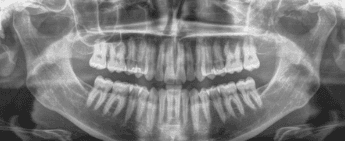

X-RAYS